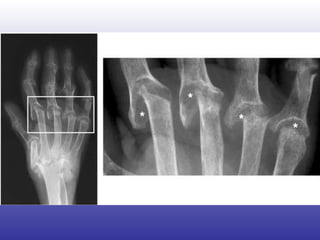

Imagenología Erosiones en cartílago y hueso Inespecíficas Rx basta Evolución daño articular: 1 año: 15-30% 2 año: 90% Otros: RNM, eco Doppler color

Imagenología Erosiones encartílago y hueso Inespecíficas Rx basta Evolución daño articular: 1 año: 15-30% 2 año: 90% Otros: RNM, eco Doppler color